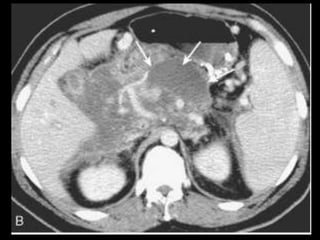

PANCREATITE AGUDA GRAVE

Ocorre em 20-30% dos pacientes com PA;

Caracteriza-se por evolução protraída, insuficiência

de múltiplos órgãos e necrose pancreática;

Necrose pode ser difusa ou esparsa, superficial ou

profunda, e pode afetar qualquer parte do

pâncreas;

A necrose ocorre logo de início, em 24-48 horas,

ela permanece estável, com raras exceções.

A administração de contraste IV é essencial,

especialmente em pacientes com PA grave, para

visualizar o pâncreas, diferenciar a glândula de

coleções líquidas adjacentes e do tecido

inflamatório peripancreático e demonstrar a

necrose pancreática.

Áreas focais ou difusas de realce diminuídas ou

ausente à TC contrastada dinâmica constituem

áreas de isquemia ou necrose.

TC tem precisão geral de 87% com S e E de 100%

para necrose extensa e 50% com áreas menores.